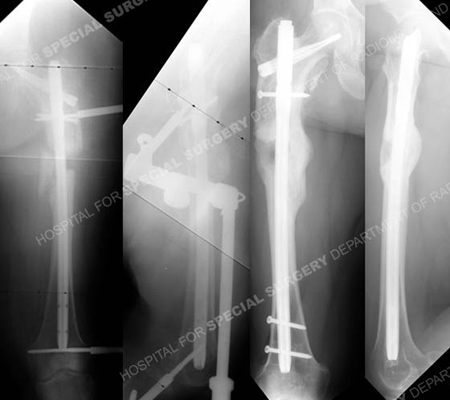

Anteroposterior and lateral radiographs (left images) immediately following the osteotomy and exchange nailing with placement of a femoral distractor for the acute limb lengthening procedure. Gradual distraction was performed over the course of 4 days with clinical monitoring and the distal interlocking screws were placed in the IM nail. The limb lengthening procedure was then complete and the femoral distractor was removed. Anteroposterior and lateral radiographs 12 months following limb lengthening (right images) illustrating a healed osteotomy in excellent alignment. Her limb lengths were equal, she reported complete pain resolution and she returned to all pre-injury recreational activities.